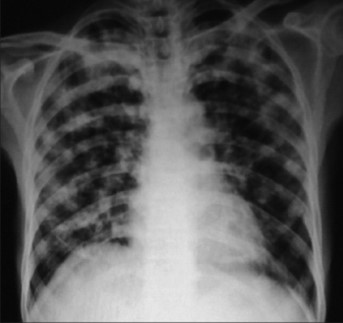

Chest x-ray showing dense opacity pleural effusion in the lower left lung of primary pulmonary TB

Pulmonary tuberculosis affects the lungs and often causes symptoms such as a chronic cough that lasts up to 3 weeks or more, chest pain, blood in cough (hemoptysis), weight loss, low-grade fever, and night sweats. When the infection spreads to other parts of the body, it is known as secondary tuberculosis.